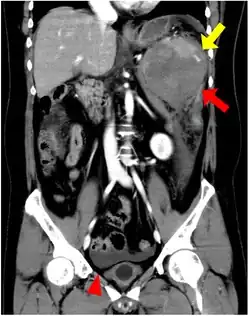

CT scan of an accessory spleen (circular object in center of image) between the spleen and left kidney.